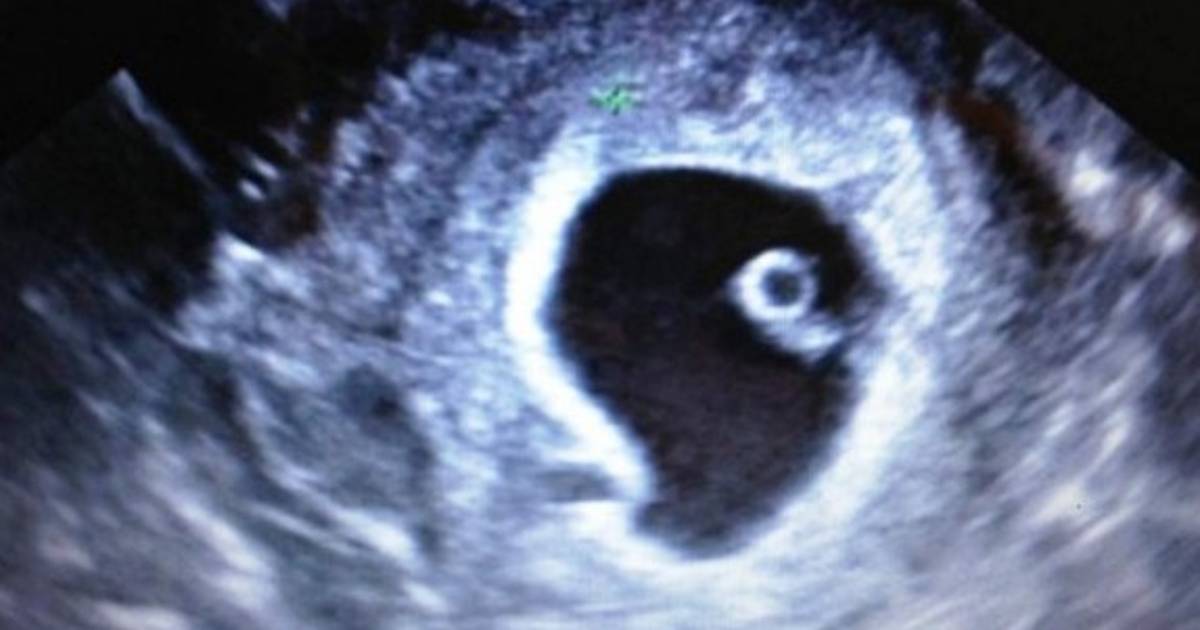

Este impactante descubrimiento fue realizado el pasado viernes por los galenos después de que la anciana, de nacionalidad brasileña, acudiera al hospital de la localidad de Palmas, capital del estado de Tocantins, tras sufrir náuseas y dolores en el estómago.

Según la ginecóloga Gesneria Saravia Kratka, la anciana le relató que hace 44 años quedó embarazada y después de sentir fuertes dolores de estómago fue a un curandero debido a que en la época no había médicos en la región donde residía denominada, Natividade.

“El hombre le dio remedios y ella dice que se sintió mejor. Su barriga no creció más, el bebé dejó de moverse y ella pensó que había abortado”, dijo la doctora a medios locales.

De acuerdo con la especialista, a pesar de que el feto murió, hubo una ‘adaptación’ en el organismo de la mujer que permitió que ella pasara 44 años sin sufrir complicaciones en su salud.

La anciana expresó a los médicos su deseo de seguir manteniendo el feto en su cuerpo, debido a que en el transcurso de los años no le había ocurrido nada, aunque los ginecólogos insistieron en la necesidad de realizar una cirugía con el fin de evitar futuras complicaciones.

“Es sobrenatural, pero ella no ha tenido complicaciones. Vamos a realizar nuevos exámenes, tomografías para ver más detalles y luego hablaremos con sus familiares para ver si nos permiten realizar la cirugía”, añadió la doctora Saravia Kratka.